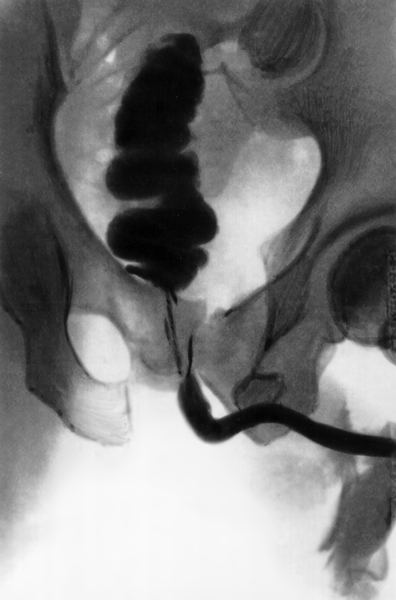

Мочевой свищ (рентгенконтрастная урография)

Мочевые свищи - это патологическое сообщение между мочевыми путями и другими органами, обусловленное в большинстве случаев травмой.